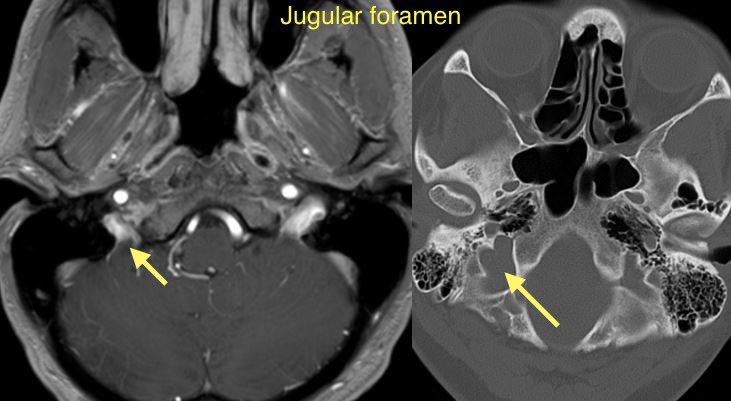

Answer: Glomus Tympanicum Paraganglioma